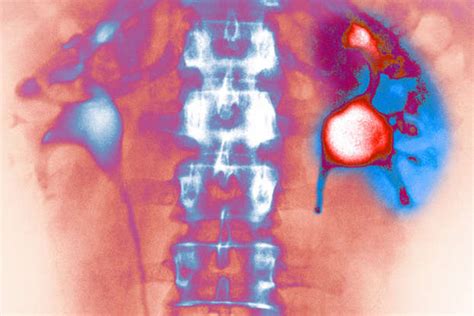

The Kidney’s Role in Waste Removal and Filtration

Let’s rewind a bit and talk about the absolute superstars of our internal filtering system: our kidneys. Seriously, guys, these organs are working 24 ⁄ 7 to keep us alive and well, and a massive part of that job is waste removal and filtration . Imagine your blood as a river carrying all sorts of things – nutrients, oxygen, hormones, but also metabolic byproducts, toxins, and excess salts. Your kidneys are the sophisticated water treatment plants that process this river. The kidney’s role in waste removal and filtration is nothing short of miraculous. Every single minute, your kidneys filter about a quarter of your total blood volume – that’s a lot of processing power! This filtering happens in tiny units called nephrons, and within each nephron, there’s a complex structure called the glomerulus. The glomerulus acts like a sieve, allowing small molecules like water, salts, glucose, and waste products (like urea) to pass through into the renal tubules, while keeping larger things like blood cells and big proteins in the bloodstream. As the filtered fluid travels through the tubules, the magic of selective reabsorption and secretion happens. Your body smartly reabsorbs the good stuff – like most of the water, essential salts, and glucose – back into the blood. At the same time, it actively secretes any remaining waste products and excess ions into the fluid. What’s left is urine, which then travels down to your bladder to be expelled from the body. This entire process is incredibly precise, ensuring that you get rid of harmful waste without losing essential nutrients or fluids. Now, think about what could go wrong. If the filtration barrier in the glomerulus gets damaged, larger molecules like proteins can leak into the urine (a sign of kidney disease). If the tubules can’t reabsorb water properly, you can become dehydrated. If waste products aren’t filtered out effectively, they build up in the blood, leading to toxic levels. This is where understanding the potential PSEglpse-1 effects on kidneys comes into play. If PSEglpse-1 is involved in maintaining the integrity of that glomerular filter, or in regulating the transport of substances across the tubular membranes, then any imbalance or dysfunction related to PSEglpse-1 could directly impair the kidney’s ability to perform these vital filtration and waste removal tasks. It highlights just how interconnected everything is within our bodies and why even a seemingly small protein could have significant repercussions on such a critical organ system. It’s truly mind-blowing!